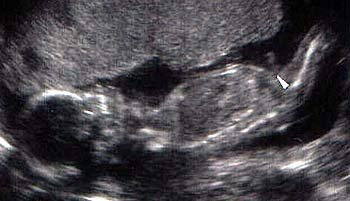

ولد في الاسبوع ال16